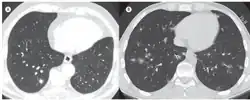

| In A, axial CT scan of the chest showing a right lower lobe pulmonary nodule surrounded by areas of ground-glass opacity (the CT halo sign). In B, axial CT scan of the chest showing multiple, randomly distributed pulmonary nodules surrounded by the CT halo sign; the final diagnosis was aspergillosis. | |

The halo sign is also understood as a region of ground-glass attenuation surrounding a pulmonary nodule on an X-ray computed tomography (CT scan) of the chest. It can be associated with hemorrhagic nodules, tumors, or inflammatory processes, but is most commonly known as an early radiographic sign of invasive pulmonary infection by the fungus species Aspergillus.